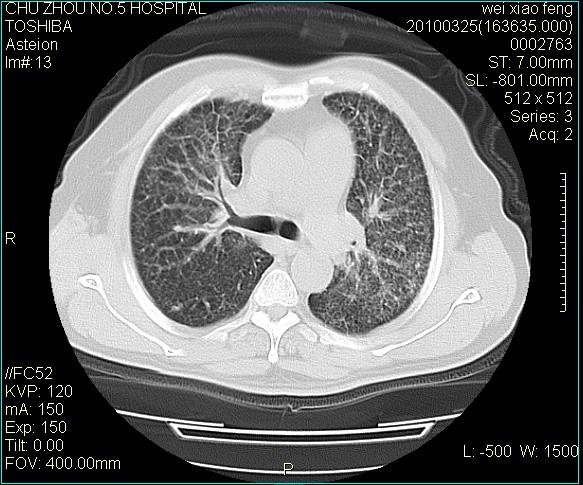

标题: CT25347:男,60岁,反复咳、痰、喘3月,加重3天。诊断??? [打印本页]

男,60岁,反复咳、痰、喘3月,加重3天。

双肺间质性改变。

考虑双肺血型潘散肺结核/

间质性肺炎伴间质纤维化!不排除伴有职业病!

双肺间质纤维化,双肺血型潘散肺结核。

考虑间质性肺炎伴间质纤维化。